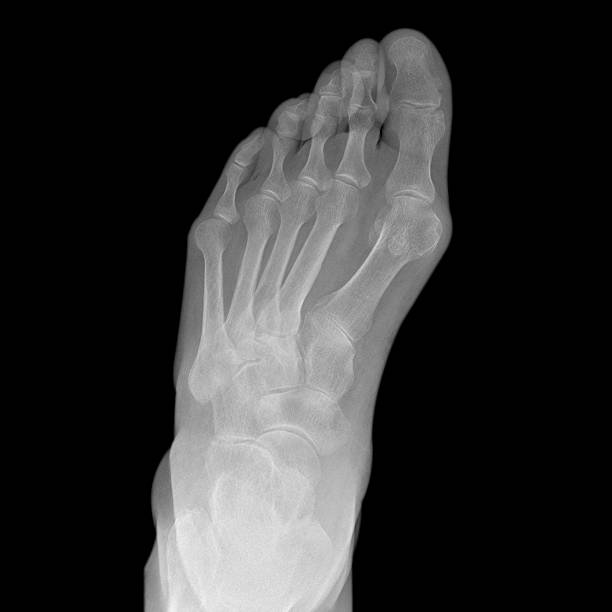

종자골염은 엄지발가락 아래쪽에 위치한 작은 뼈인 종자골(sesamoid bone)에 염증이나 통증이 발생하는 질환으로, 주로 반복적인 압력이나 충격으로 인해 발생합니다. 이 부위는 체중이 집중되는 부위 중 하나로, 보행이나 운동 시 지속적으로 자극을 받기 쉬우며, 특히 하이힐을 자주 신거나 달리기, 점프 등의 활동을 자주 하는 사람에게 잘 나타납니다. 종자골염은 초기에는 가벼운 통증으로 시작되지만, 시간이 지남에 따라 발바닥 앞쪽의 통증이 심해지고, 걸을 때 불편함을 초래하거나 발을 디딜 때 찌릿한 통증이 느껴지는 등 일상생활에 큰 영향을 미칠 수 있습니다. 본 글에서는 종자골염의 주요 원인 10가지를 중심으로, 나타나는 증상과 진단 방법, 그리고 효과적인 치료법과 재발 방지를 위한 관리법에 대해 구체적으로 살펴보겠습니다.

발의 해부학적 구조 이상, 즉 평발이나 요족(높은 아치)은 종자골염의 발생 가능성을 높이는 요소입니다. 평발은 발바닥 전체가 지면에 닿는 구조로, 충격 흡수가 비효율적이며 체중이 앞발로 과도하게 실리는 경향이 있습니다. 반대로 요족은 발의 아치가 비정상적으로 높은 형태로, 걸을 때 충격이 종자골 등 일부 부위에 집중되면서 피로와 통증을 유발할 수 있습니다. 이러한 구조적 문제는 발바닥 근육과 인대에 지속적인 부담을 주고, 그로 인해 종자골 부위에 만성적인 염증이 발생할 수 있습니다. 특히 아치의 균형이 깨지면 보행 패턴도 왜곡되어 종자골을 비롯한 발의 다양한 부위에 손상이 일어날 수 있습니다. 따라서 해부학적 구조에 이상이 있는 경우에는 기능성 깔창이나 아치 지지 보조기구를 사용해 하중을 분산시키는 것이 중요합니다. 또한 개인의 발 형태에 맞춘 신발 선택과 족부 전문가의 상담을 통해 증상을 예방하고 개선할 수 있습니다.

종자골염의 대표적인 증상은 발 앞쪽, 특히 엄지발가락 아래 부위의 통증입니다. 이 통증은 서 있거나 걷거나 뛸 때 더욱 심해지며, 장시간 활동 후에는 발바닥이 욱신거리거나 짓눌리는 느낌이 들 수 있습니다. 일부 환자는 국소적인 부기나 압통, 열감을 느끼기도 하며, 통증으로 인해 발을 절거나 무의식적으로 보행 자세가 바뀌는 경우도 있습니다. 증상이 심해지면 신발 신는 것조차 불편해지고, 심한 경우 발을 디디기 어려운 상태에 이를 수 있습니다. 특히 뻣뻣한 바닥을 맨발로 걸을 때 통증이 뚜렷해지며, 뼈를 누를 때 날카로운 통증이 느껴질 수 있습니다. 종자골염은 만성적으로 진행되는 경우가 많아 조기에 적절한 관리가 이루어지지 않으면 지속적인 통증과 활동 제한이 동반되며, 이로 인해 일상생활의 불편과 삶의 질 저하로 이어질 수 있습니다. 따라서 초기 증상을 인지하고 빠르게 대처하는 것이 매우 중요합니다.